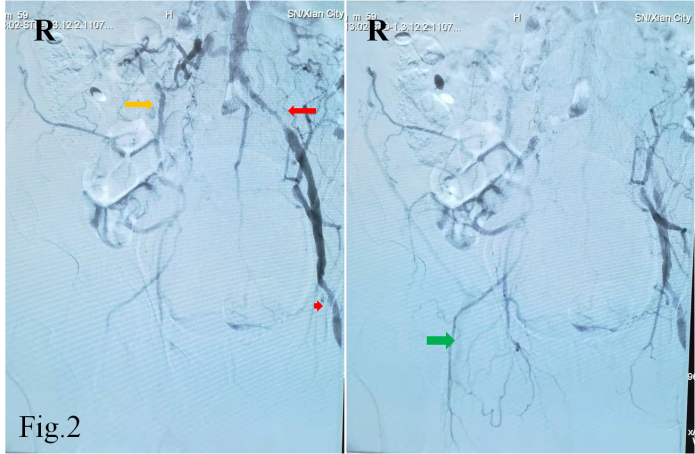

55岁的白先生因急性脑梗死入住啄木鸟 神经内科,双侧颈部血管、锁骨上窝均可闻及血管杂音,为详细评估脑血管情况,拟行全脑血管造影检查。常规的脑血管造影检查首选右侧股动脉穿刺入路完成造影,但是该患者存在明确的右下肢间歇性跛行病史,双侧股动脉搏动触摸不到。下肢动脉超声提示双侧股动脉中度狭窄,股动脉、腘动脉等下肢血管动脉粥样硬化斑块形成。仔细评估后,考虑无法从股动脉穿刺进行造影检查。经神经介入医生周密准备,拟进行经右侧桡动脉穿刺完成脑血管造影及下肢血管造影检查。

经过导丝引导下,谨慎地将造影导管置于主动脉弓,造影显示Ⅱ型主动脉弓,介入医生顿感压力倍增。常规路径下(股动脉置管),Ⅱ型主动脉弓要比Ⅰ型主动脉弓操作难度复杂的多,颈部血管从主动脉弓发出角度、走形、迂曲度及造影导管在主动脉弓如何塑形、塑形成功率等等都会制约操作时间、顺畅性,稍有不慎可能导致主动脉弓斑块脱落、主动脉动脉夹层等情况发生。增加了在经桡动脉在Ⅱ型主动脉弓上超选造影的难度。经介入医生耐心、细致操作下,反复尝试降主动脉造影导管成型,逐步“逆行”完成全脑血管造影及下肢动脉造影。